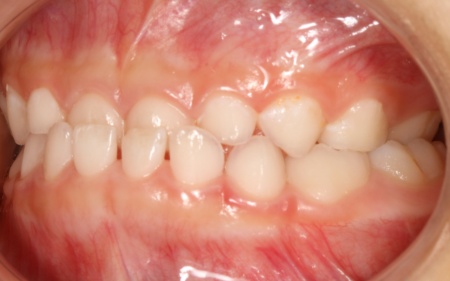

治療後

お子様の成長に合わせて慎重に治療を進めることで、無理のない自然な形で歯並びと噛み合わせを改善することができました。